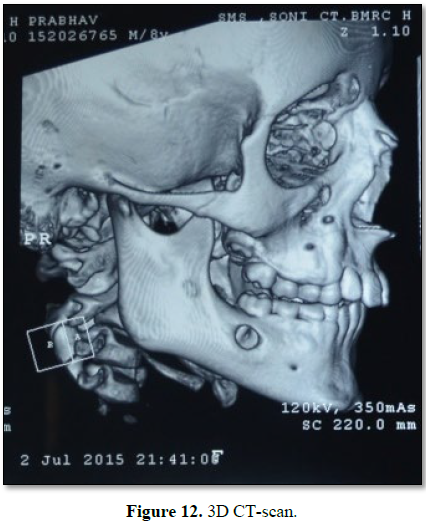

Thereafter 3D-CT scan was done for precise evaluation and assessment of

the lesion which showed bone destruction/perforation of cortical plate in that

region, representing its aggressive nature (Figure 3).

Similar case

with exactly similar clinical presentation, radiographic finding,

histopathological reporting and immediate recovery after similar intervention

procedure irt to 46. The only difference was that this lesion was unilateral (Figures 10-14).

CT scan showed excessive bony thinning and destruction with resorption of

buccal cortical plates, showing signs of its aggressive nature.